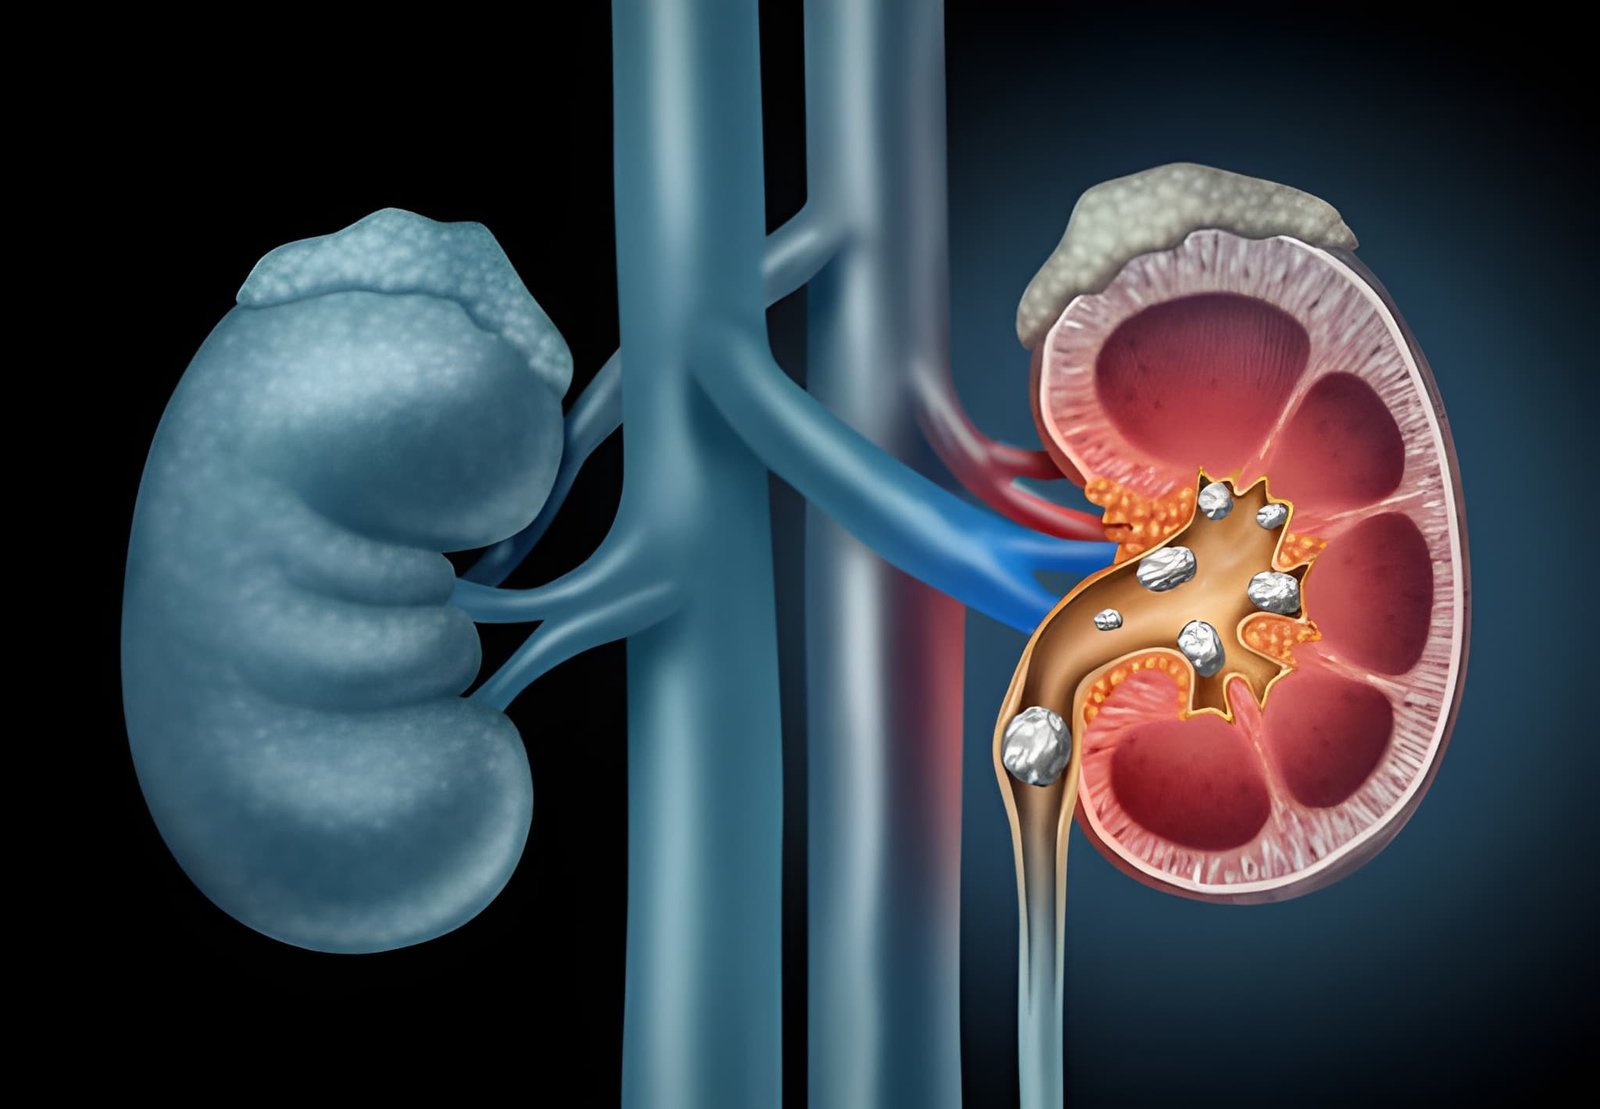

Percutaneous Nephrolithotomy (PCNL) is a minimally invasive surgical procedure used to remove kidney stones that are too large to pass naturally or cannot be treated effectively with other methods.

The term “percutaneous” means through the skin. During this procedure, a small incision is made in the back to create a pathway directly to the kidney. Through this pathway, the surgeon inserts specialized instruments through a thin tube to locate, break, and remove the kidney stones.

PCNL is commonly recommended for large, complex, or multiple kidney stones, especially when other less invasive treatments are not suitable or have not been successful.

When large kidney stones block multiple branches of the kidney's collecting system (known as staghorn stones).

When kidney stones are larger than 2 cm (0.8 inches).